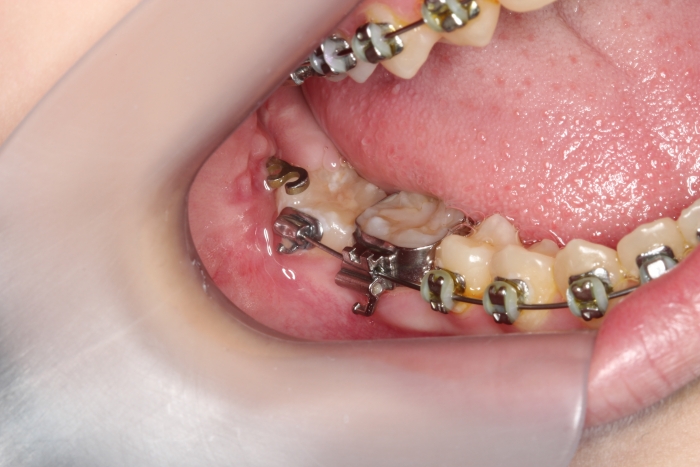

Extração dos 4 terceiros molares   - Instalação de placas de ancoragem - Clínica Cliniface

Extração dos 4 terceiros molares - Instalação de placas de ancoragem